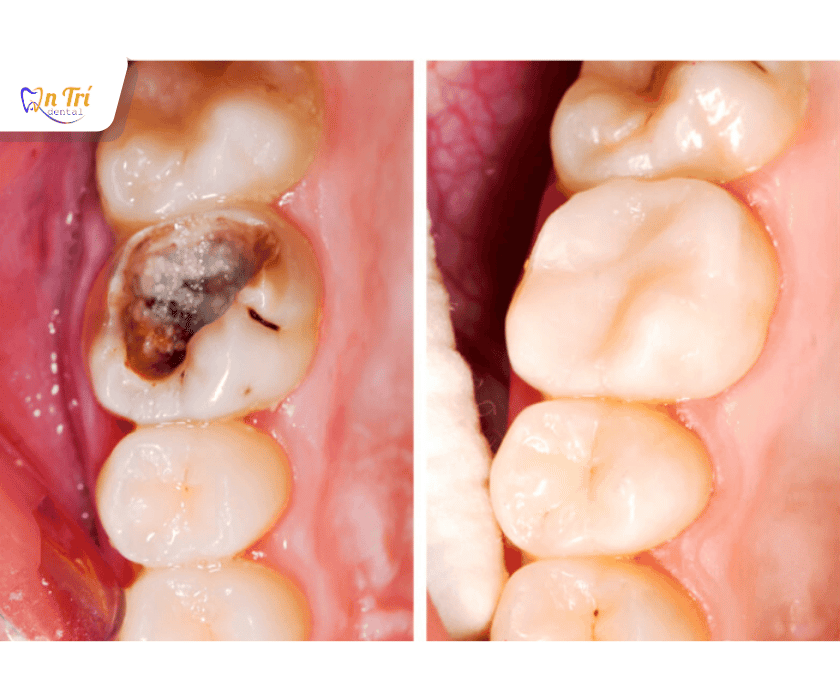

Phục hồi răng nhờ trám thẩm mỹ

Sâu răng, sứt mẻ răng là những vấn đề phổ biến, không chỉ gây mất thẩm mỹ mà còn ảnh hưởng trực tiếp đến chức năng ăn nhai và sức khỏe răng miệng. Trám răng, hay hàn răng, từ lâu đã là một giải pháp cơ bản để khắc phục các khuyết điểm này. Tuy nhiên, với sự phát triển của công nghệ, trám răng thẩm mỹ đã ra đời, không chỉ phục hồi mà còn tái tạo vẻ đẹp tự nhiên của răng, giúp bạn tự tin nở nụ cười mà không lo bị lộ miếng trám.

Trám răng thẩm mỹ là kỹ thuật nha khoa sử dụng vật liệu trám có màu sắc tương tự với màu răng thật để lấp đầy các khoảng trống do sâu răng, sứt mẻ, hoặc mòn men. Mục đích chính của phương pháp này là khôi phục hình dáng ban đầu của răng, bảo vệ tủy răng khỏi vi khuẩn và trả lại chức năng ăn nhai bình thường.

- Sâu răng: Khi răng bị sâu ở mức độ nhẹ và trung bình, trám răng sẽ loại bỏ mô sâu và lấp đầy lỗ hổng, ngăn ngừa vi khuẩn tiếp tục tấn công vào tủy răng.

- Răng sứt mẻ, vỡ: Các trường hợp răng bị sứt mẻ nhỏ do va chạm hoặc nhai vật cứng, trám răng giúp phục hình lại hình dáng răng, bảo vệ răng thật khỏi bị tổn thương nặng hơn.